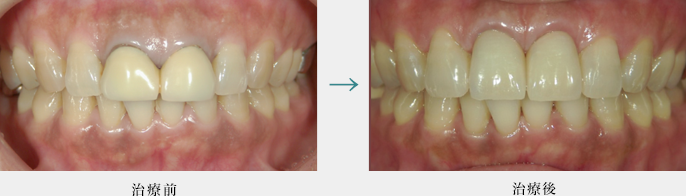

ダイレクトボンディング

ダイレクトボンディングは歯を大きく削らずに直接口腔内で材料を接着硬化させることで、歯の隙間や形態を修復する方法です。

ダイレクトボンディングにより前歯の隙間を改善